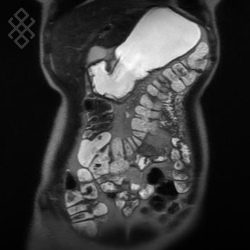

Entéro-IRM

Vous entrez dans l'aimant, ouvert des 2 côtés, les pieds en premier et allongé sur le dos. Pour recueillir le signal et construire les images, vous aurez une antenne sur l'abdomen. Étant donné que cet examen est bruyant, vous aurez à votre disposition des tampons auriculaires pour atténuer le bruit de la machine.

La durée moyenne de l'examen est de 30 min. Dans le cas d'une injection, le manipulateur en radiologie vous administrera le produit de contraste. Vous entendrez un bruit caractéristique à l'IRM faisant penser à un marteau piqueur.